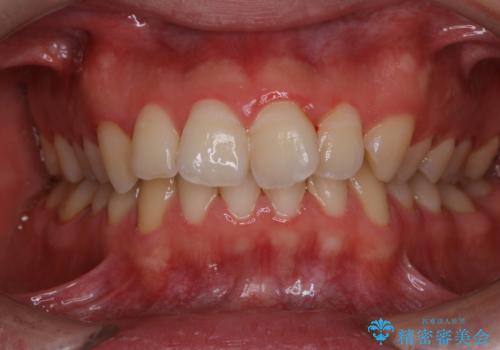

人生初めて歯のクリーニング(PMTC)

- 今まで歯医者で、クリーニングを受けたことがないため綺麗にしたいとのことでした。PMTC60分コースを行いました。